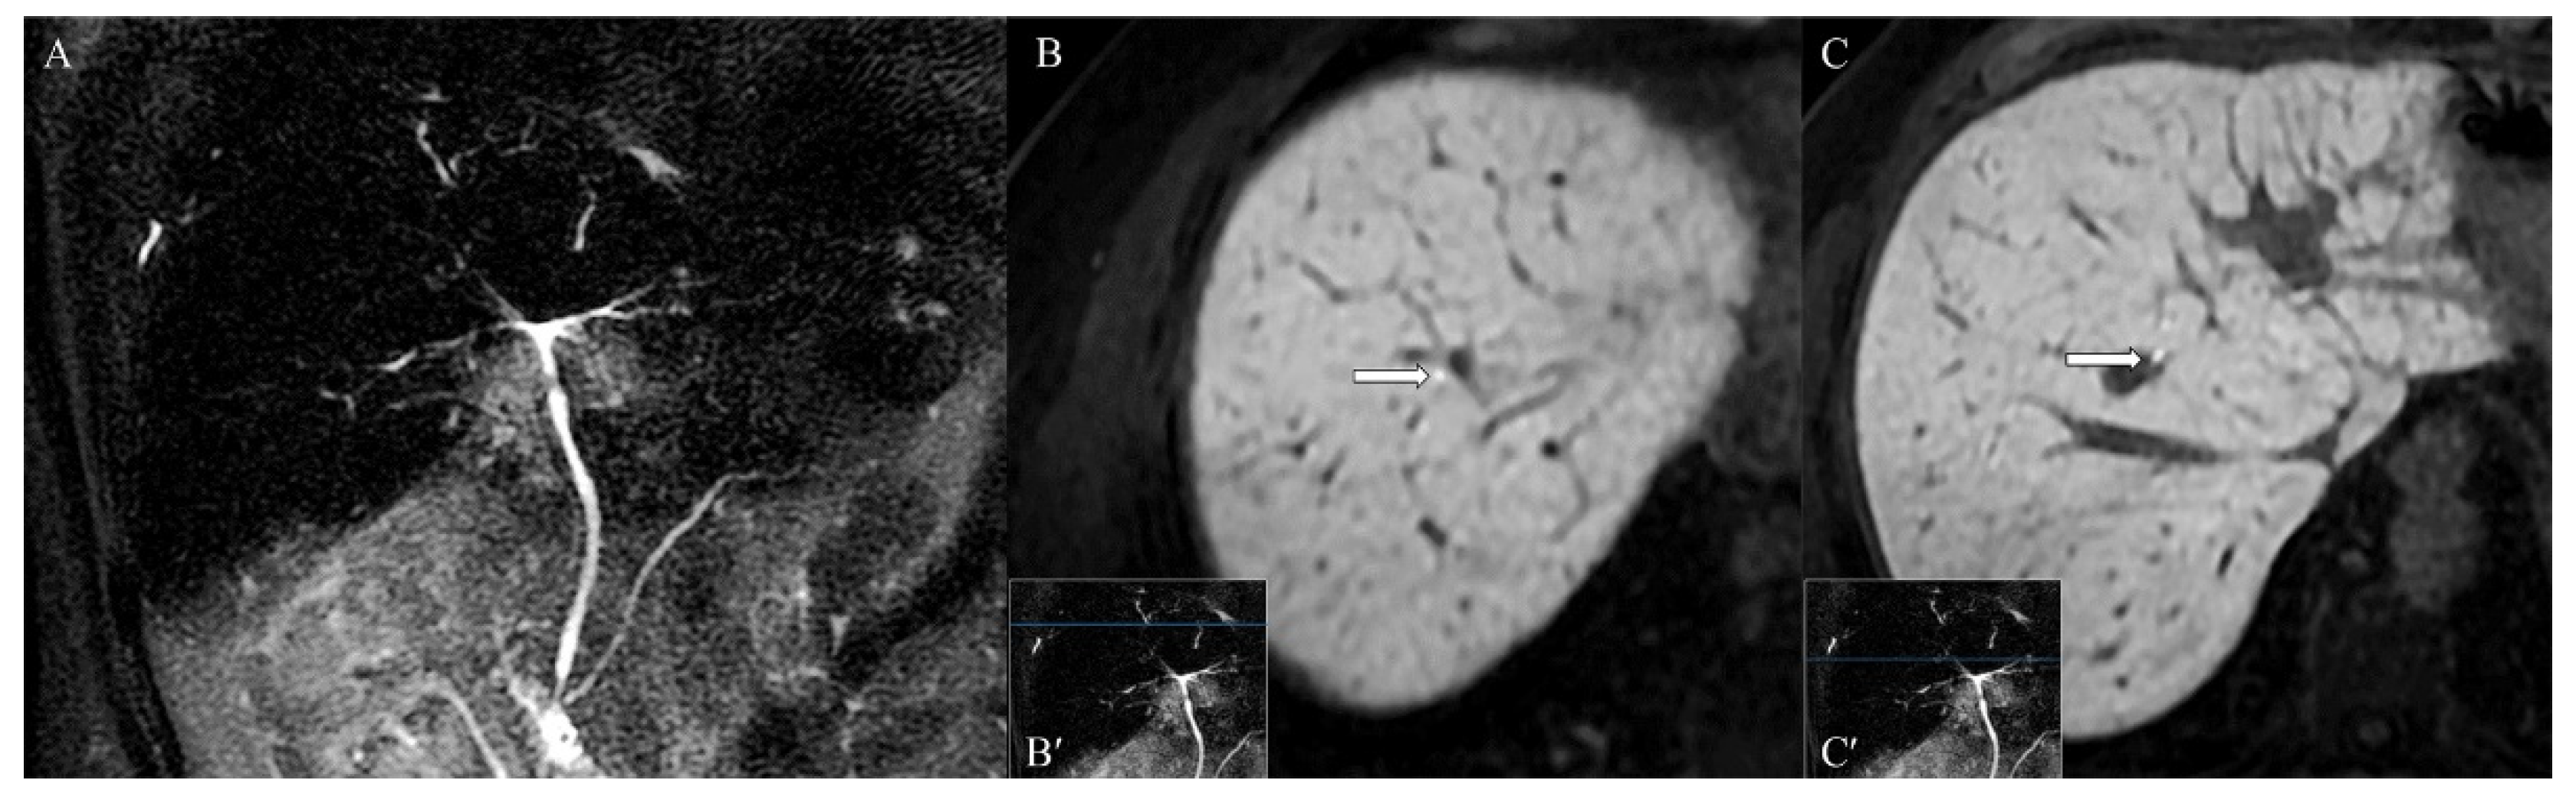

Furthermore, the course of few intrahepatic bile ducts appeared focally restricted, without upstream dilation (Figure 5A). The functional MRCP demonstrated that the excretion of the contrast medium in the biliary tracts was maintained in the physiological time (Figure 5B,C).

Figure 5.

(A) MRI cholangiography phase, in the absence of anamnesis, does not allow a confident differential diagnosis with primary sclerosing cholangitis. (B,C) After administration of Gd-EOB-DTPA, hepatobiliary phase images (B) above and (C) below the stenosis demonstrate physiological opacification of the intrahepatic bile ducts and, despite the stenosis, physiological contrast flow.

Moreover, our case is the first in the literature to present a functional MRCP evaluation of the biliary ducts in a patient with diagnosed systemic sarcoidosis and hepatobiliary involvement after endovenous administration of Gd-EOB-DTPA. The use of this contrast medium in the study of the biliary tree is off-label, but it is very helpful in the differential diagnosis of focal liver lesions [46]. Therefore, in the case of the study of unknown hepatobiliary lesions, the use of this new contrast medium allows us to obtain high diagnostic performances on both the hepatic parenchyma and the biliary tract [46]. Furthermore, in patients diagnosed with sarcoidosis—such as ours—according to a recent meta-analysis, the relative risk of developing liver cancer is not negligible [47]. Furthermore, the imaging of the bile ducts obtained in the delayed phase of the study allowed us to rule out primary sclerosing cholangitis based on the focal distribution of the narrowings, the absence of upstream dilations, and the evidence of contrast material proximal and distal to the apparent filling defects, indicating that there were no flow-limiting lesions.